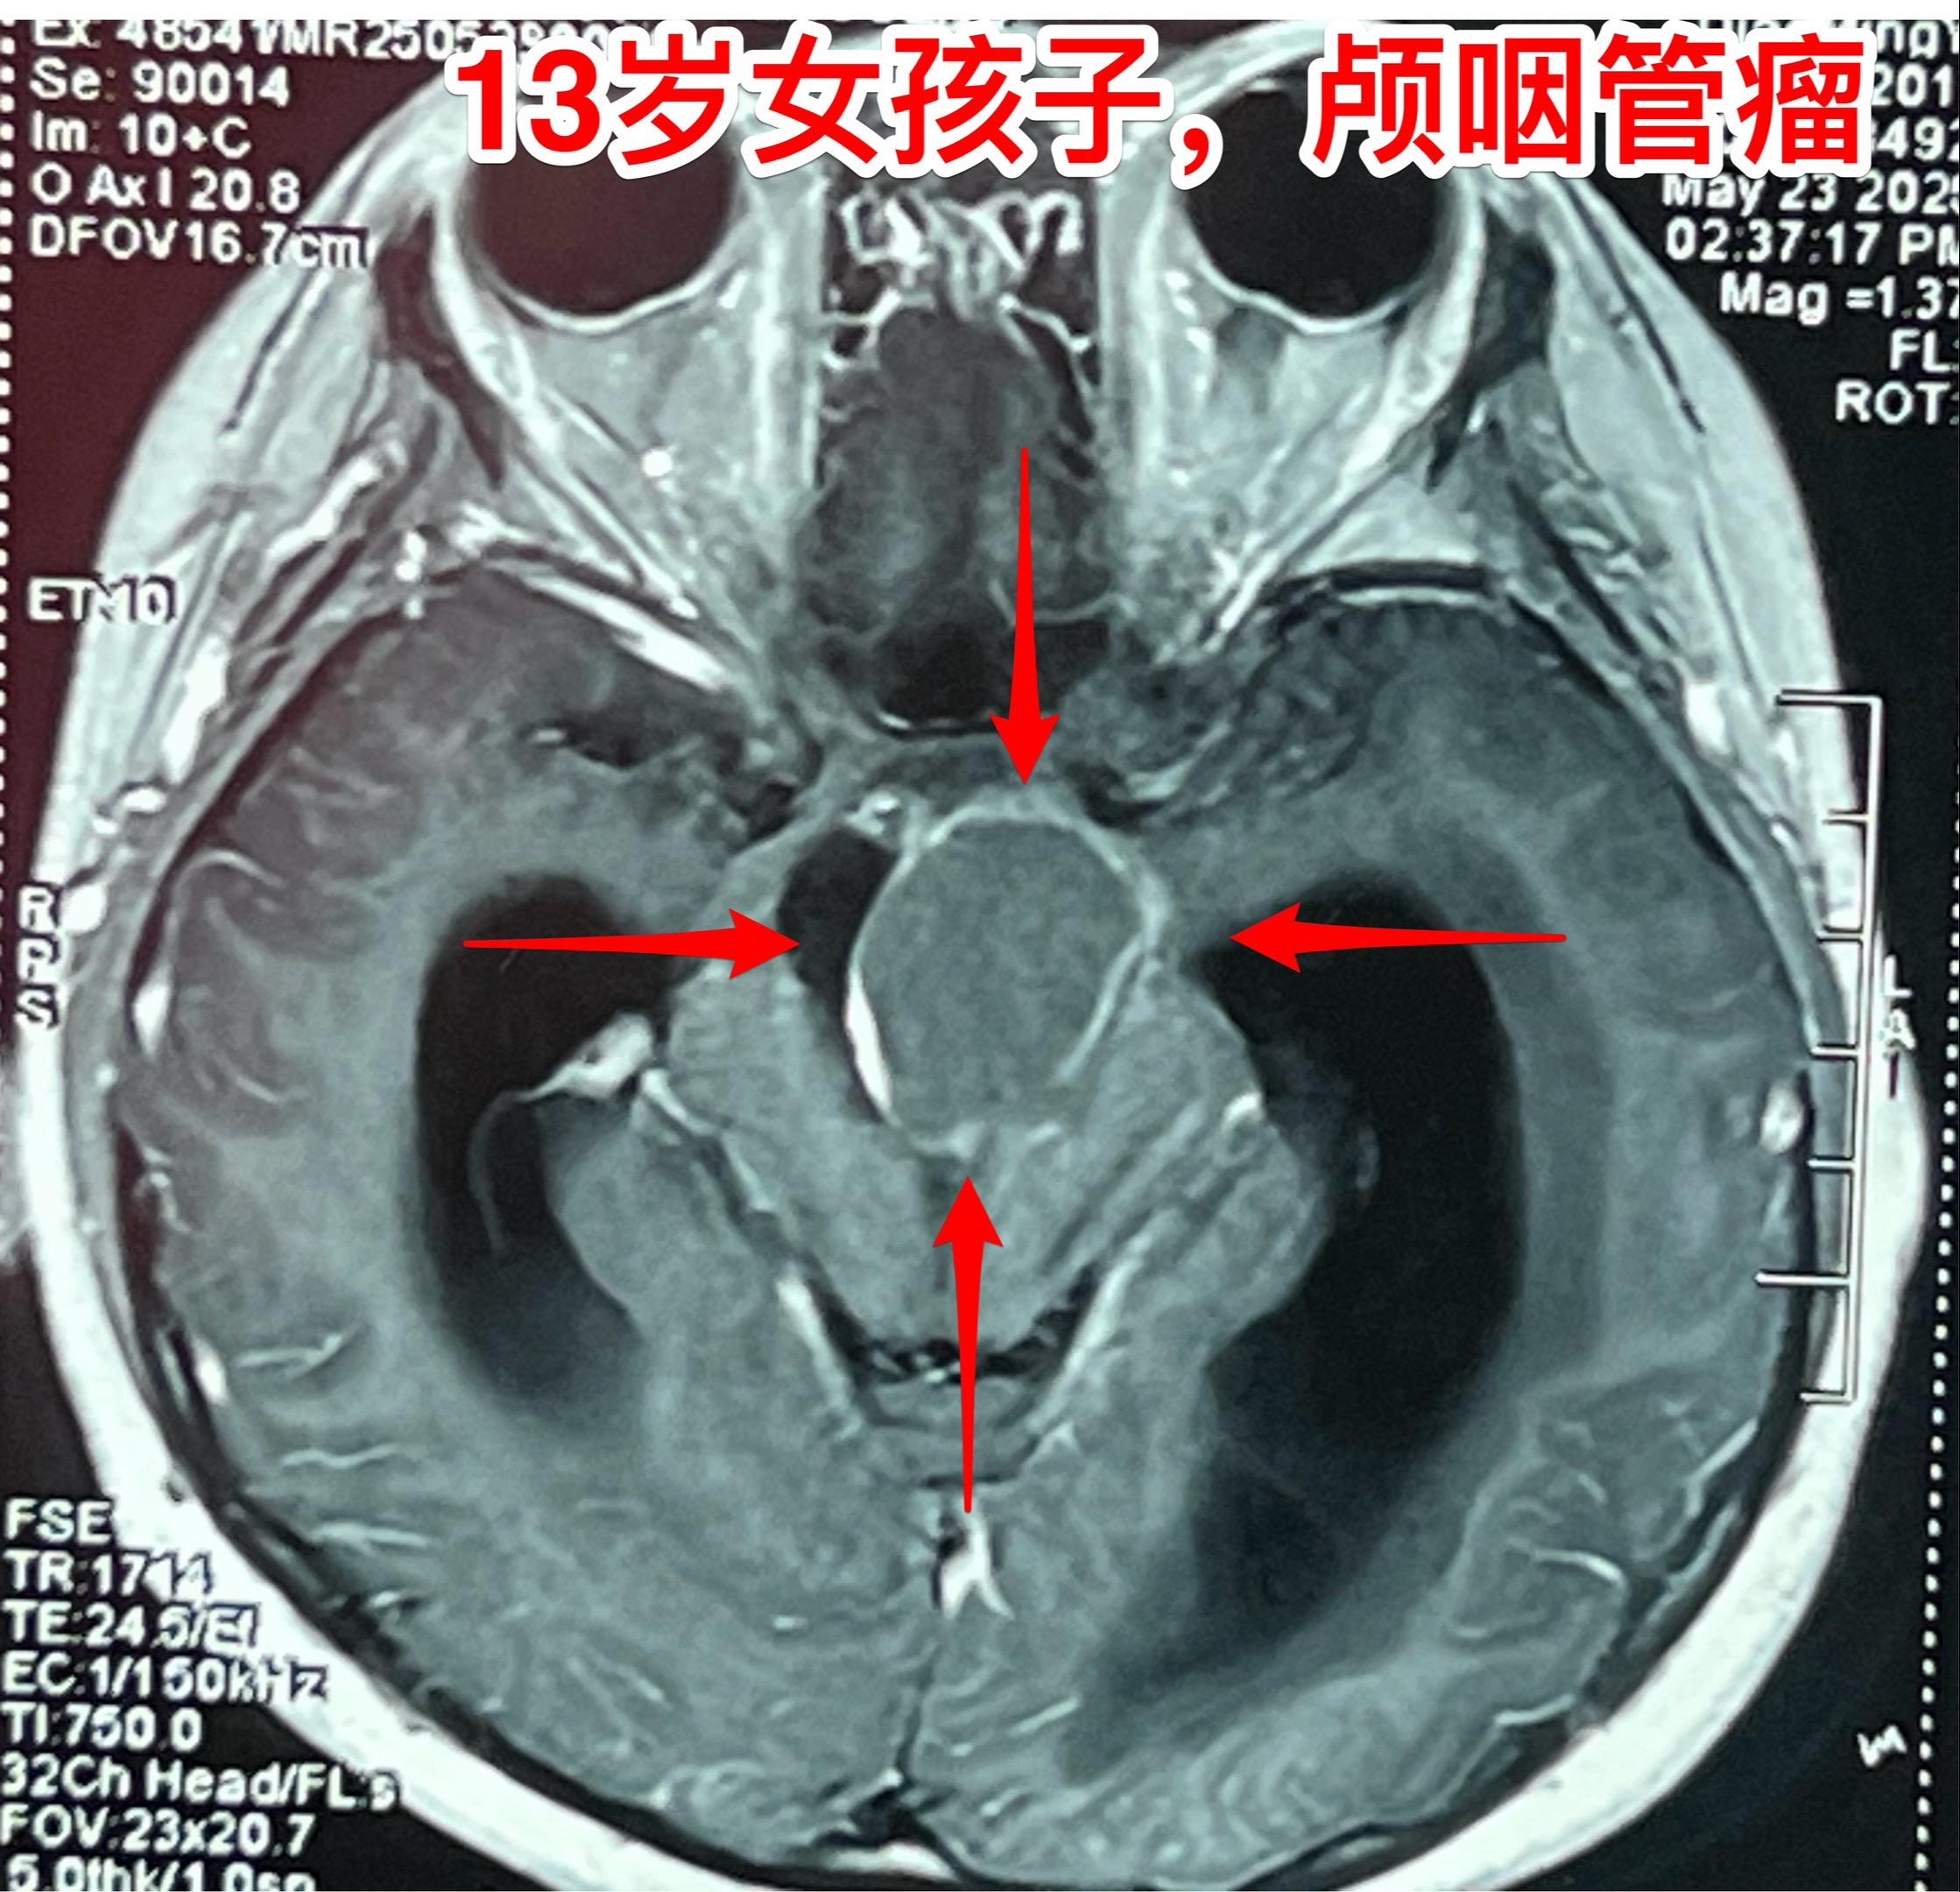

孤独症小孩子5月30日作了颅咽管瘤手术。来自新疆克拉玛依的13女孩子,在2岁时诊断为孤独症,经过家长的不懈努力,加上科学训练,小孩子的生活能力大有改善。 不幸的是,今年小孩子因为头痛、呕吐、行走不利行脑部检查发现了鞍区肿瘤,怀疑是颅咽管瘤,伴有脑积水。在我院住院后经过降颅压治疗、皮质激素治疗,她的头痛、呕吐症状有好转,但是行走不利症状无显著改善。 5月30日作了开颅手术,将肿瘤完全切除。手术后CT结果令人满意。希望她能顺利出院。